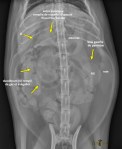

Latérale annotée